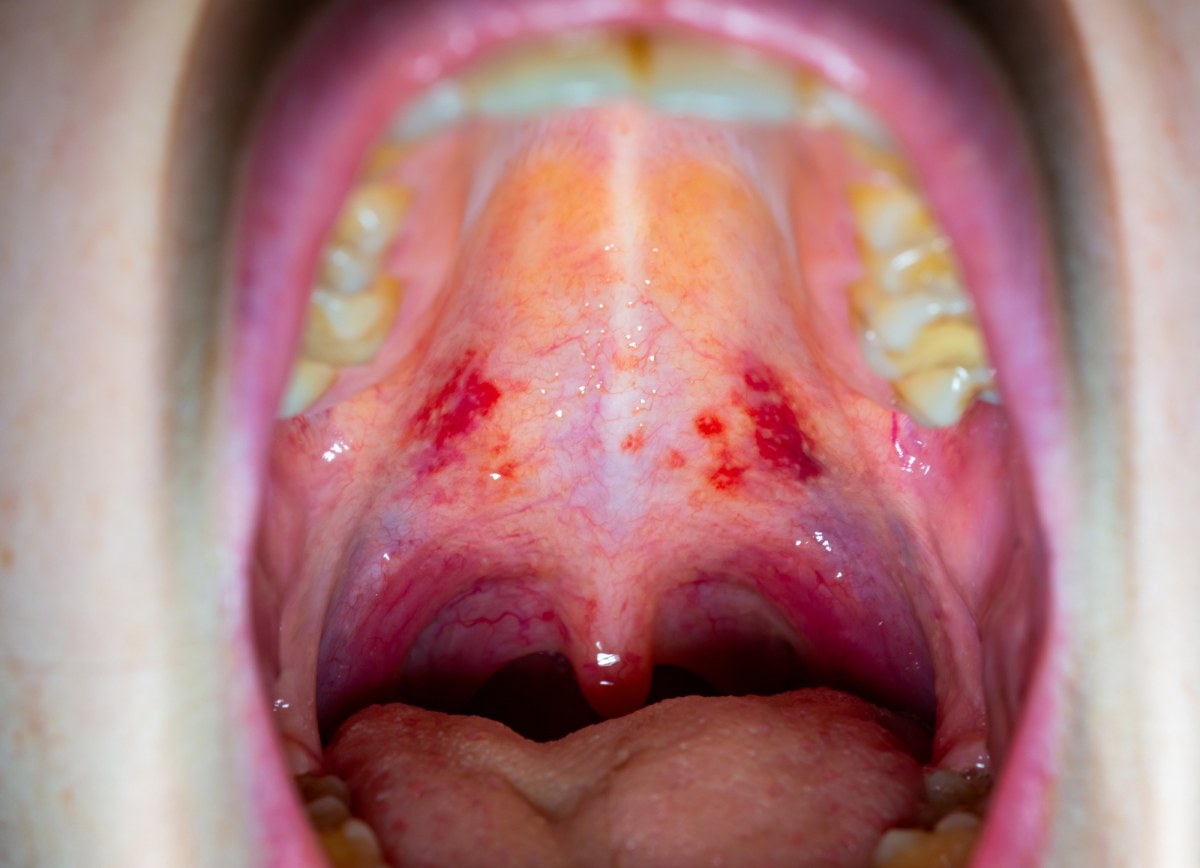

Nowe warianty COVID-19. Nietypowe objawy, "gardło ...